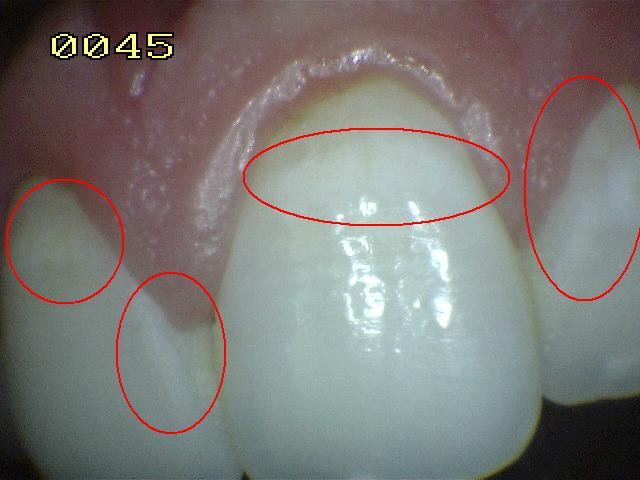

Código 0: No

hay evidencia de caries en esmalte seco.

- Secado por 5 segundos

- No debe haber evidencia de caries. Las

superficies con defectos de desarrollo, tales como la

hipoplasia del esmalte,

fluorosis, desgaste de los dientes

(abrasión y erosión), y las manchas extrínsecas por ingerir

mate, te y café; ó el hábito de fumar o manchas

intrínsecas por fluorosis,

tetraciclina u otra sustancia, debe

codificarse como 0.